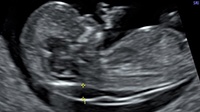

Hội chứng Down ở thai nhi có thể được tiến hành sớm từ tuần thứ 11 của thai kì.

Hiện nay, để sàng lọc Hội chứng Down, có thể sử dụng các test huyết thanh và siêu âm tầm soát lệch bội. Có 2 test huyết thanh căn bản là Double test và Triple test.

Siêu âm tầm soát Hội chứng Down ở cuối tam cá nguyệt thứ nhất (khi tuổi thai từ 11 tuần đến hết 13 tuần) có thể khảo sát được: